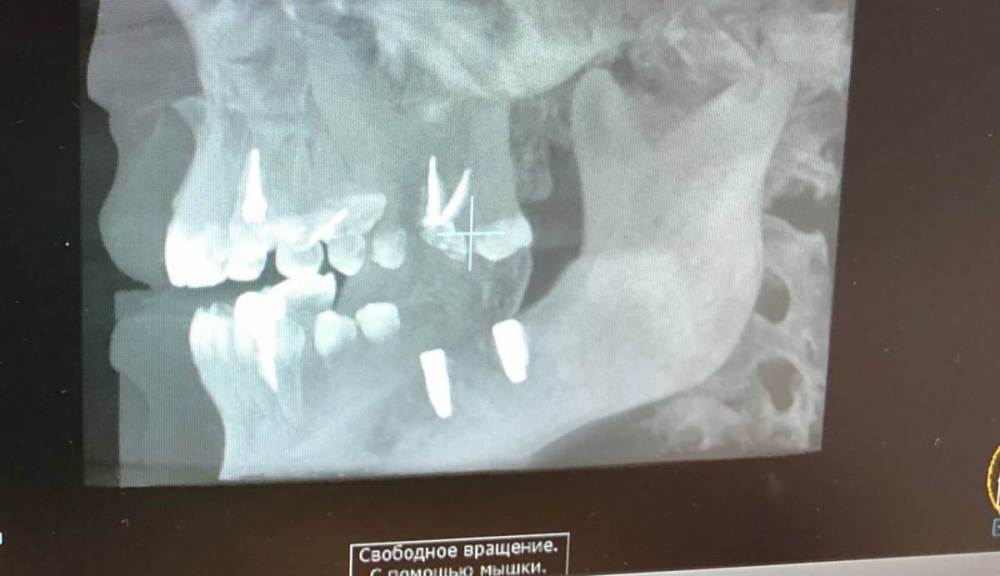

Stoyana Опубликовано 22 мая, 2023 Поделиться Опубликовано 22 мая, 2023 Здравствуйте ! Прошу прокомментировать замену имплантов . 10 лет назад были установлены 2 импланта , 6 на место удаленного зуба , и 7 - в качестве антагониста верхней 7 . Устанавил тот же доктор , по гарантии . Приняли решение заменить импланты , так как коронка с 6 сломалась , на 7 сломался абатмент . После операции , очень болит 5 , ноющая боль , плюс болезненные ощущения при глотании , болит челюсть в области операции . Доктор утверждает что по снимку проблем нет . Прошу прокомментировать ситуацию . Первые 2 фото - импланты которые заменили . 3 и 4 фото - новые импланты Ссылка на комментарий